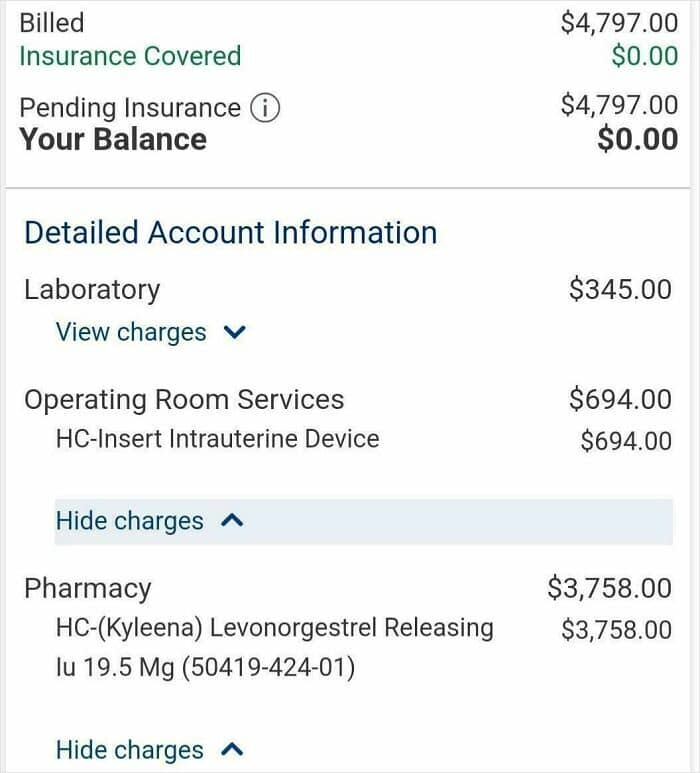

#29 My Gyno Is Trying To Charge My Insurance (That I Know Will Try To Argue It) For An Iud I Didn’t Receive

So I went in to get an IUD, but couldn’t get it done since my gyno didn’t have the proper dilator at the clinic and was told I’d have to get it done at the hospital, thats all fine and dandy. Well then I decided to check my health portal since the appointment hadn’t posted last time I had logged in, low and behold they’re trying to charge me for an IUD I did not receive. Like you really think my insurance won’t bat an eyelash when I have another appointment for an additional IUD.